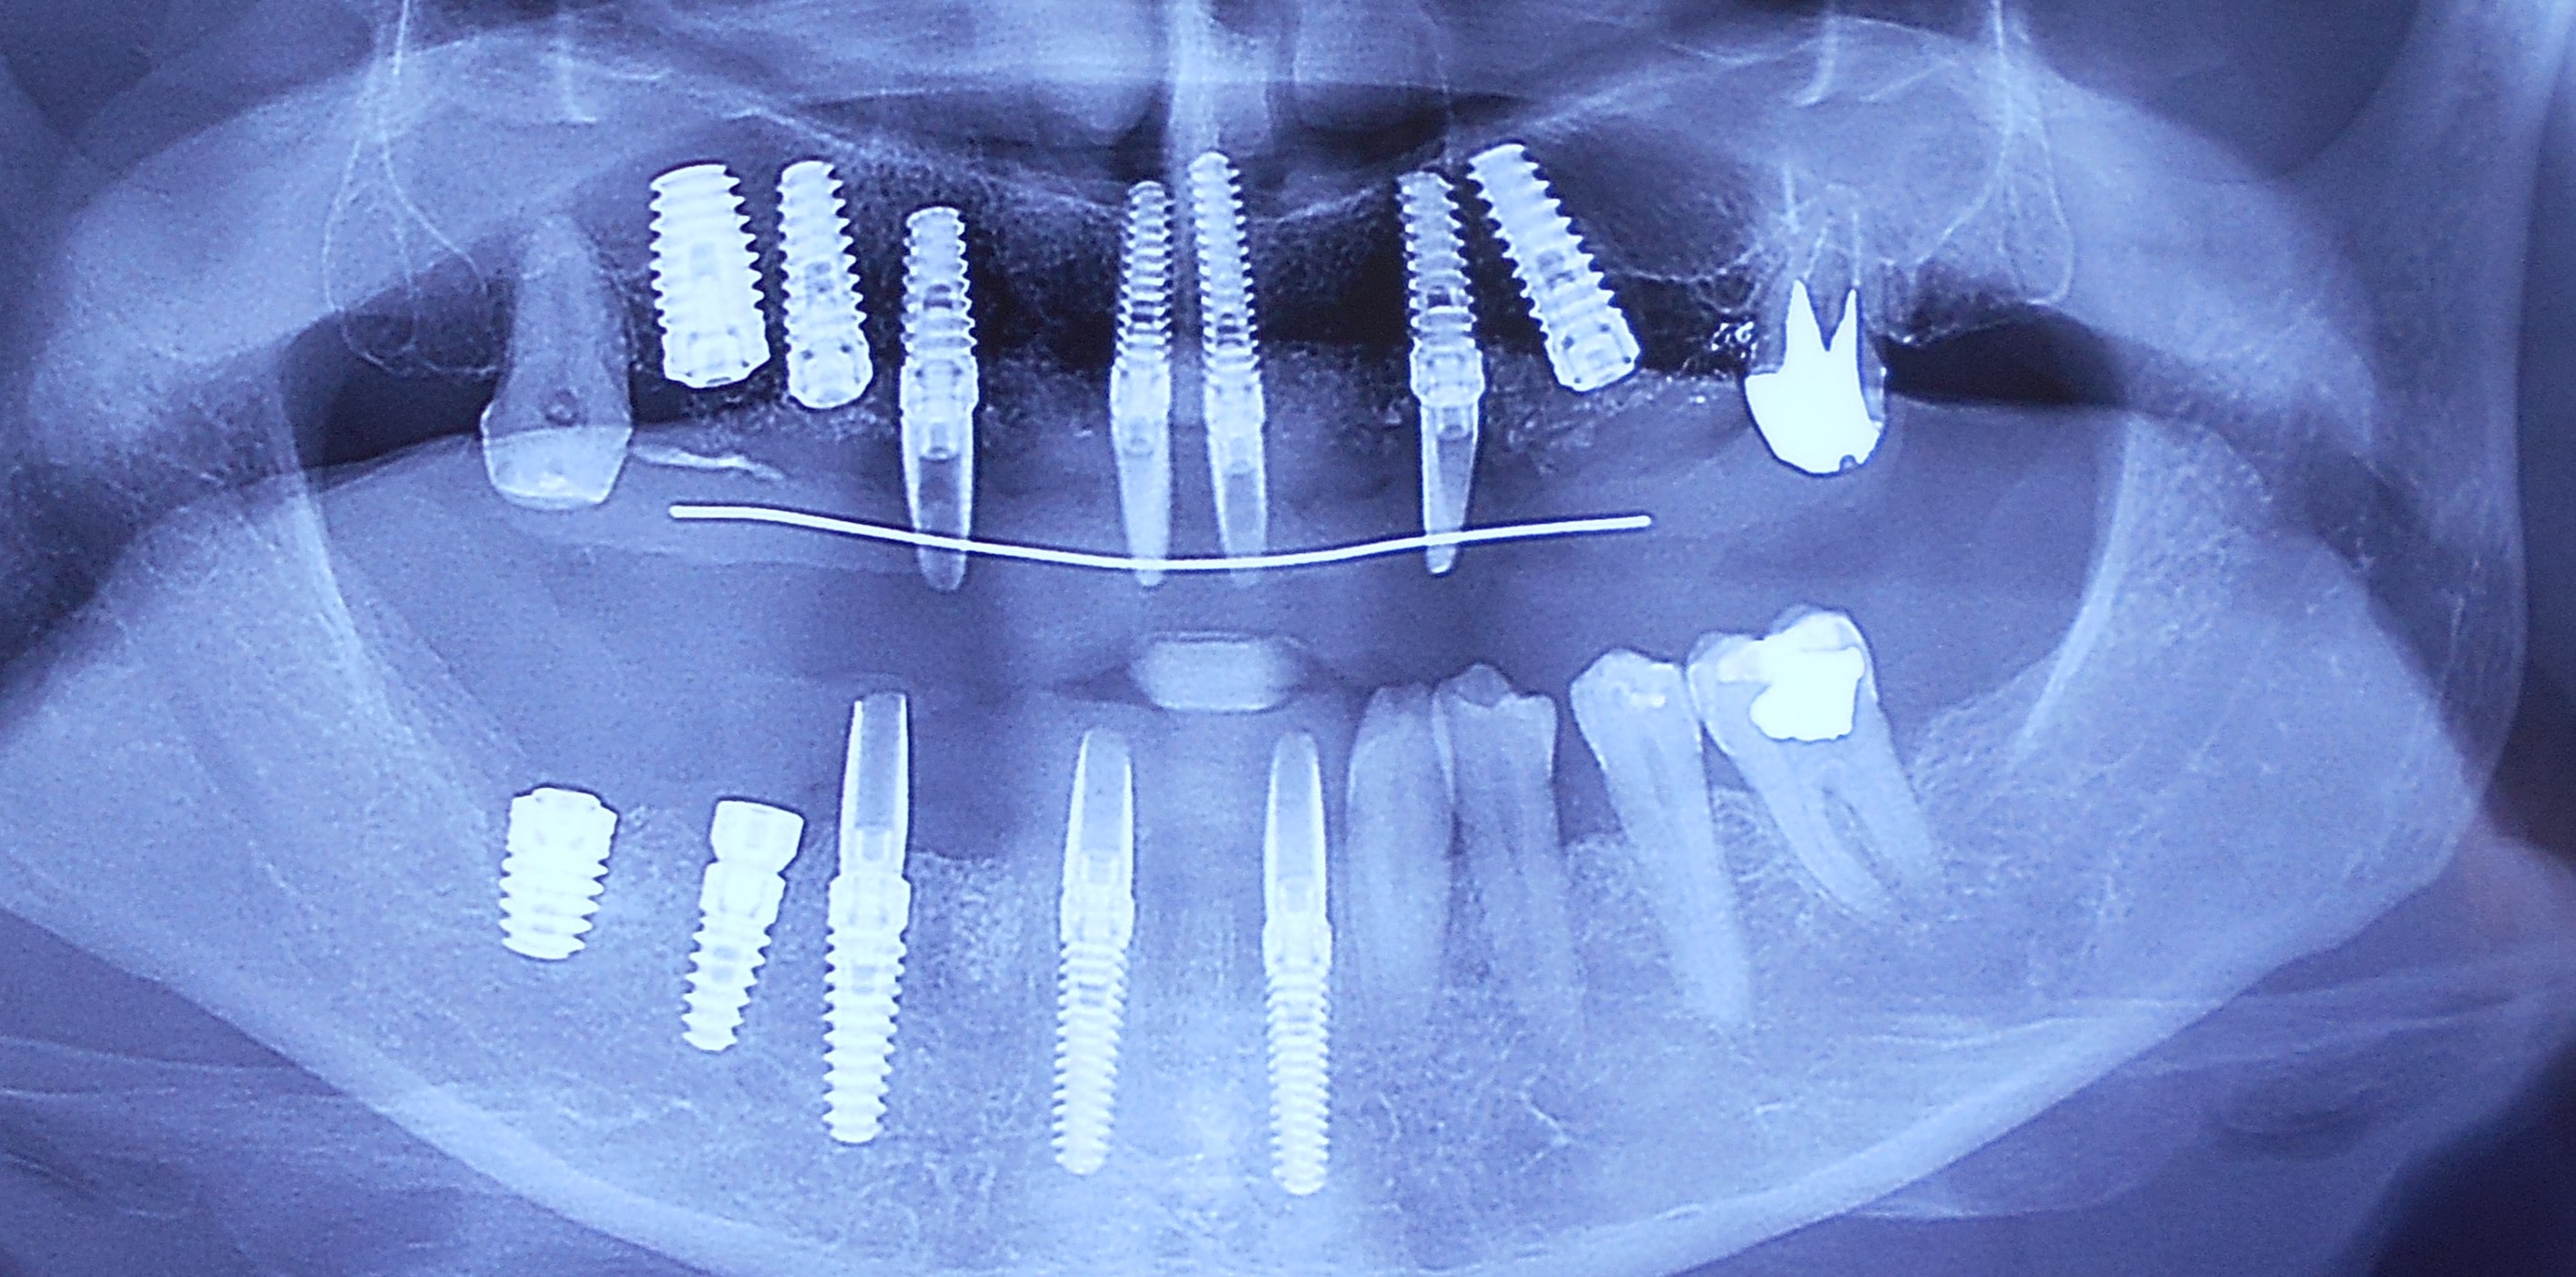

Pacijent dolazi sa starim mostovima i izraženom parodontopatijom u donjoj vilici. Urađeno je skidanje postojećih mostova i istovremena ekstrakcija svih parodontopatičhin zuba uz ugradnju sedam implantata u gornjoj vilici i pet implantata u donjoj vilici. Pacijent je nakon tri dana bio privremneo protetski zbrinut sa fiksnim privremeni krunicama koje su fiksirane na tek ugrađenim implantaima. Nakon četiri meseca je izrađen fiksni cirkonijum kermički- bezmetalni most u gornjoj i donjoj vilici. Rad uspešno završen pre tri godine.